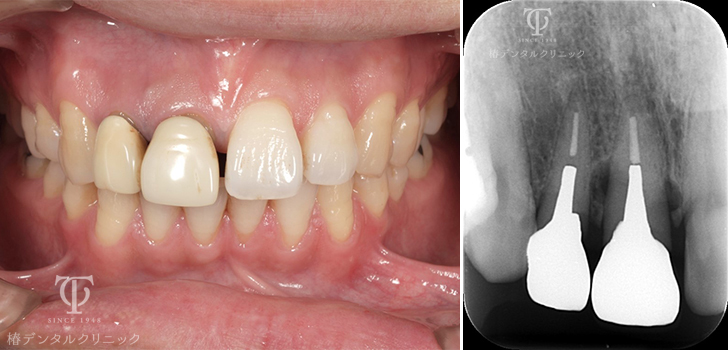

Case05

歯根破折の為、前歯が位置異常をおこしていました。

残った歯を部分矯正治療で引っ張り硬組織・軟組織を再生させました。

術前

術後

- 症状

- 前歯を綺麗にしたい

- 治療期間

- 約1年半

- 治療費用

- 部分矯正治療:330,000円×2

インプラント治療:473,000円

オールセラミッククラウン:165,000円

歯根破折をおこし前歯が位置異常をおこし綺麗にしたいということで来院されました。残った破折歯を部分矯正治療に利用して骨造成を回避しました。

【リスク・副作用】

インプラント治療後、痛みや違和感、出血、腫れなどが出る事があります。喫煙者、糖尿病などの方の場合、歯が生着しない場合があります。